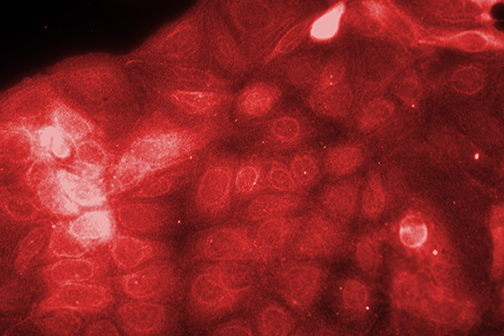

LSU Health New Orleans Researchers Discover a Key Failure in AMD that May Lead to Progression & Vision Loss

Research led by Nicolas Bazan, MD, PhD, Boyd Professor, Ernest C. and Yvette C. Villere Chair for the Study of Retinal Degeneration, and Director of the Neuroscience Center of Excellence at LSU Health New Orleans School of Medicine, suggests that age-related macular degeneration (AMD) decreases an essential fatty acid, preventing the formation of a class of protective molecules and reducing repair potential. The discovery may also open new therapeutic avenues for AMD. More